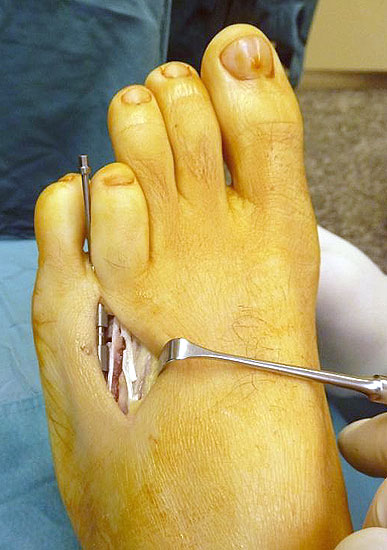

Das im Folgenden vorgestellte Operationsverfahren beschreibt die Kallusdistraktion von Metatarsalia nach den Prinzipien von Ilisarov 21 unter Verwendung eines internen, winkelstabilen Titan-Minifixateur (Klauser 2009). Der interne Distraktor ermöglicht während der Distraktions- und der Durchbauungsphase aufgrund seiner hohen Stabilität je nach Modell (18 mm, 23 mm) eine Verlängerung von bis zu 25 mm. Nach interner Anlage des Minifixateurs, meist lateral, kann über eine kontinuierliche Kallusdistraktion der Metatarsalebogen unter frühzeitiger Mobilisation im Gips oder Short-Walker rekonstruiert werden 15. Über einen interdigital und transcutan ausgeleiteten Aktivatorstab wird die Distraktion vom Patienten selber täglich morgens und abends durchgeführt. Zusätzlich vorliegende Strahlpathologien, wie zum Beispiel eine verkürzte Strecksehne oder ein kontraktes Metatarsophalangealgelenk können im Rahmen der Erstoperation ebenso therapiert werden wie z.B. ein Hallux valgus, ein Hallux valgus interphalangeus und/oder ein Digitus quintus varus (Klauser 2009). Nach Rekonstruktion des Metatarsalebogens wird in einem zweiten, kleinen Eingriff der Aktivatorstab über eine Spezialpinzette diskonnektiert und entfernt, wobei der Distraktor als interne Fixation belassen wird. Die Entfernung des Distraktors erfolgt in der Regel nach 9 – 12 Monaten, da es sich meist um angeborene kindliche Fehlbildungen handelt (Brachymetatarsie) und eine operative Intervention frühzeitig im Kindesalter erfolgen sollte (Klauser 2009).

• Zweiter Eingriff: Diskonnektieren des transcutan ausgeleiteten Aktivator, falls möglich, über eine kleine Inzision von 1,5 bis 2 cm, in der Regel jedoch über Eröffnen der alten Schnittführung mit ggf. Strecksehnenverlängerung und erneutem Grundgelenk-Release sowie ggf. Ausleiten einer Penroselasche oder einer Gentamycin-Palacos-Minikette.